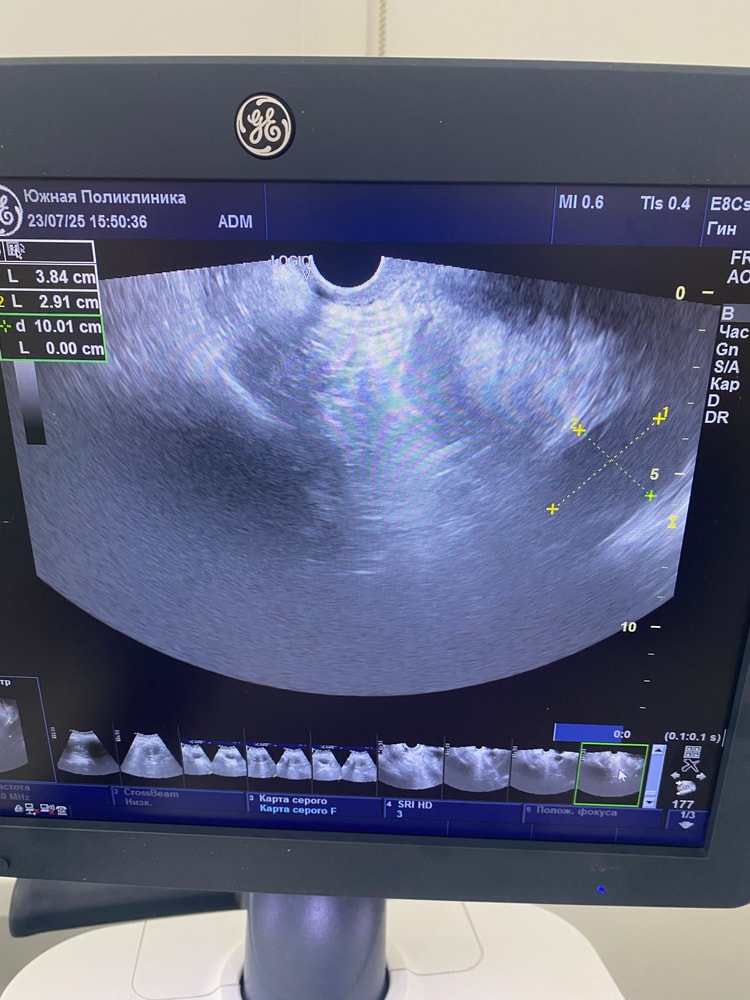

Гинекологические заболеванияНачну с того, что делала фолликулометрию и на 13 ДЦ фолликул был 1,5 см. Ждала овуляцию, с 16 дц начались какие то боли как при О, но не прошли в тч 1-2 дней. Сегодня на 20ДЦ пошла на узи, нашли какую то кисту, вроде с перегородками она сказала. Или с чем то на букву «П». Могу путать. Размер 4.5 см. Желтого тела нет, фолликула моего того тоже нет. Откуда эта киста взялась если её не было неделю назад? Заключения нет, есть фото. Девочки кто разбирается, посмотрите пожалуйста 🙏🏻

врач в ЖК сказала просто наблюдать, это обычная киста которая бывает у всех. Но она не знает что киста с перегородками. А чат gpt выдал что это не хорошие признаки(((